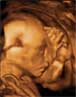

En la semana 20 de embarazo, el feto ya mide 20 centímetros (desde la coronilla al coxis) y pesa alrededor de 250 gramos. La ecografía en 2D que se recomienda ahora se hace un estudio muy detallado de la morfología del bebé para descartar malformaciones y confirmar que su desarrollo es el correcto.

Ecografía 2D de un feto de 20 semanas de perfil

En este momento mide 20 centímetros de la cabeza a los pies.